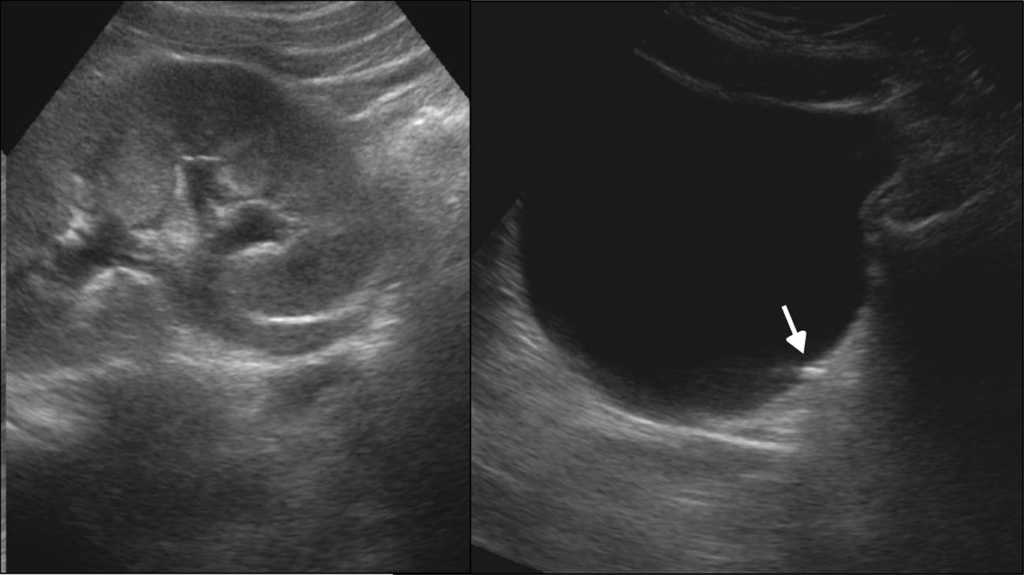

Entre las consultas m??s comunes que requieren procedimientos diagn??sticos en pediatr??a, se encuentran el dolor abdominal y los v??mitos. Si bien antes se indicaban estudios radiol??gicos, sus principales causantes (estenosis hipertr??fica de p??loro, malrotaci??n, v??lvulo, obstrucci??n secundaria del intestino e invaginaci??n intestinal, entre otras) pueden ser descartadas o confirmadas por ultrasonido2.

En el caso del neonato, la ecograf??a transfontanelar es de suma utilidad porque posibilita el diagn??stico de hemorragias intracraneales y la leucomalacia periventricular, las dos entidades m??s frecuentes en el prematuro (figs. 17 y 18).

Adem??s, en reci??n nacidos la ecograf??a debe ser el m??todo inicialmente elegido ante la sospecha de malformaciones cerebrales, hidrocefalia cong??nita, mielomeningocele, hidronefrosis y malformaciones nefrourol??gicas, hernia diafragm??tica, hemorragia suprarrenal, enteritis necrotizante, torsi??n testicular intra??tero y ovariocele, entre otros diagn??sticos.